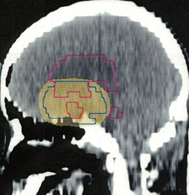

MRIでみえる腫瘍の領域を腫瘍体積 (GTV)といいます

これは退形成性星細胞腫グレード3のフレア画像と言います。白く見える部分が腫瘍なのですが,どこまでが腫瘍なのかMRIでもわかりにくいものです

オレンジの色がGTVではっきり腫瘍と断定できるところです

グリオーマはMRIでみえる以上に広がっているので,腫瘍の周囲を十分に囲む領域を照射します,それを臨床的標的体積 (CTV)といいます

赤紫の線で囲った部分の内側で,びまん性グリオーマの場合は,GTVから20mmくらいの距離を取るのが普通です

さらに少し (0.3-0.5cm) 領域を広げてかけ損じのないようにするので治療計画表的体積 (PTV)といいます,上の図では赤紫の2本の線の外側にあたります

薄茶色に塗った部分には計画54グレイの90%以上の線量が入ります

この体積の決め方は腫瘍の形や悪性度によっても変わってきます

放射線治療医の腕の見せ所です

実際に放射線があたるのはPTVの領域です

この例の治療計画でとても大切な点は,腫瘍のある左前頭葉には放射線が十分入っているのですが,右前頭葉の被曝は最低限に抑えられている点です

両側の前頭葉の対照的な被曝では認知機能が著しく低下することを知っている放射線治療医だからできることです

ここには,脳腫瘍の治療で良く用いられる(拡大)局所照射,全脳室系照射,全脳照射の治療計画と脳にあたる線量の分布を図にしてあります。実際に視床下部/下垂体にできた胚腫ジャーミノーマの患者さんに,25.2グレイを14回に分割してかける計画を立てた時のものです。上から順に局所照射,全脳室照射,全脳照射となっていますから,この照射がどのようなものかを理解する手がかりにしてください。青い線はCTV,黄色く塗ったのはPTVです。

腫瘍局所照射

トルコ鞍(下垂体)と視床下部にある腫瘍の部分だけに当てる照射です。目的の場所には25.2グレイが入ります。同時に脳の25%くらいの容積に15グレイが入っています。ジャーミノーマにこの方法を使うと放射線の当たっていない脳室から高率に再発します。

右側のグラフの黄色いところの面積が脳に入る放射線の合計量です。同じ25グレイでも局所照射と全脳照射ではずいぶん違う量が入っているのが判ると思います。放射線を当てる広さのことを照射野 radiation field といいます。